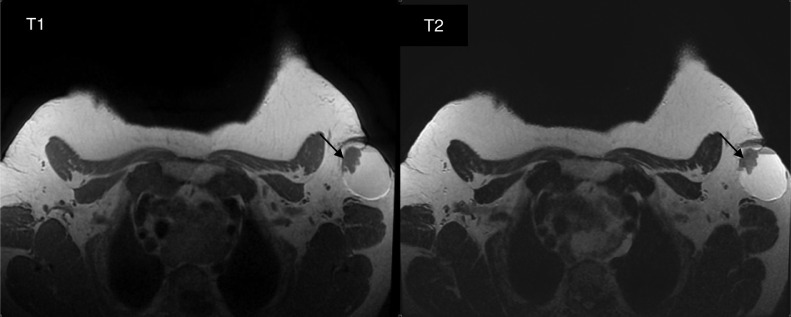

Fig. 7.

Axial T1- and T2-weighted images show the solid component (arrows) that appears hypointense in T1 with intermediate T2 signal.